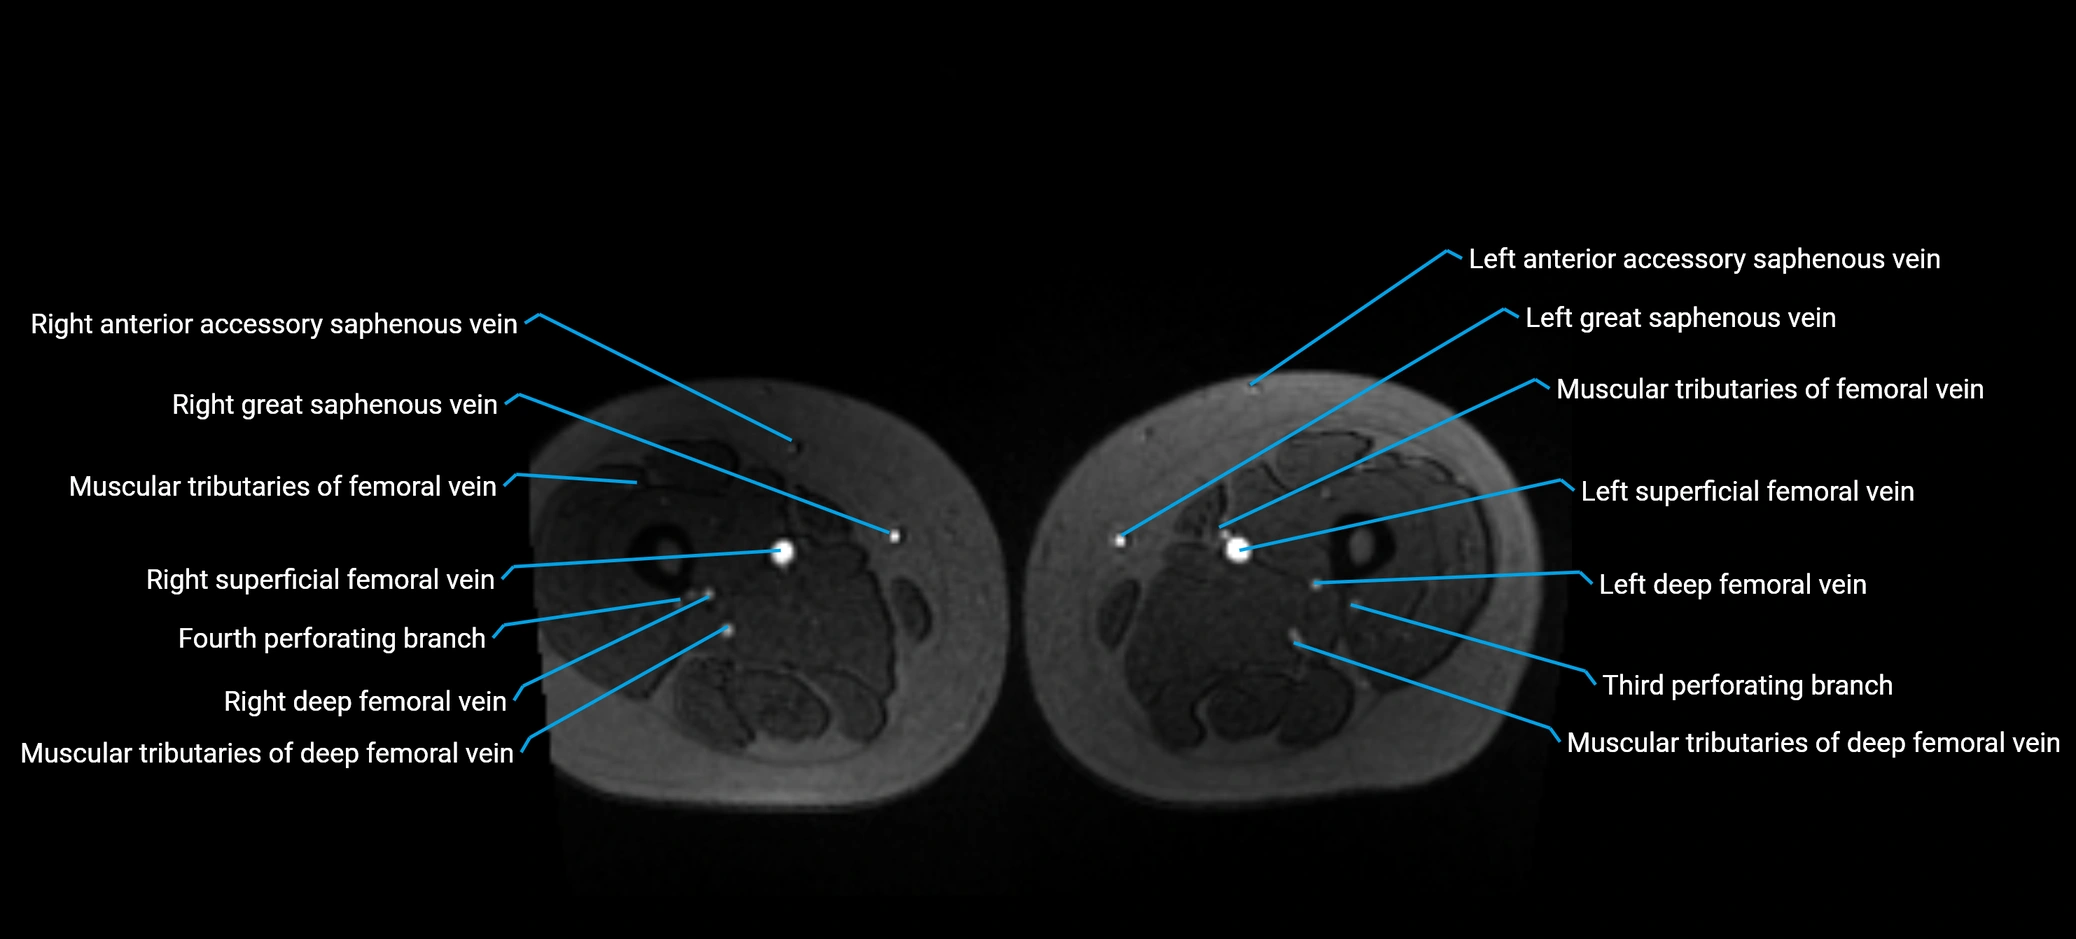

MRI image

image